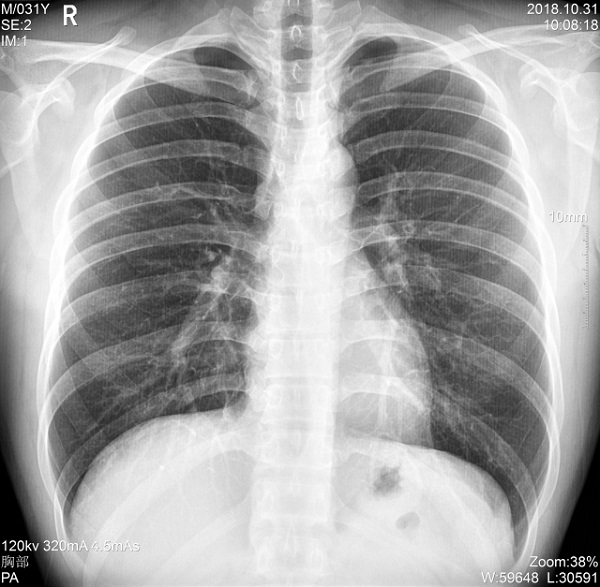

三、支持高千伏攝影 肺部紋理更有層次

PLX5500系列移動DR的可調(diào)千伏達(dá)到150kV,在達(dá)到一定高電壓后,與骨骼相重疊的軟組織或骨骼本身的細(xì)小結(jié)構(gòu)及含氣的管腔等,均可清晰顯示。